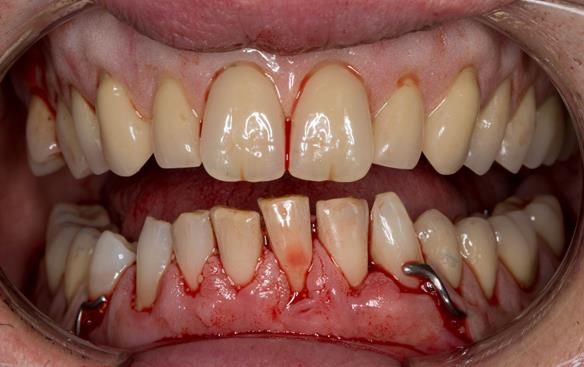

This 52 year old man was referred to me from his general dental practitioner in 2018.

10 years prior to consultation the patient's general dentist diagnosed periodontitis and referred him to Manchester Dental Hospital. He received a treatment plan to manage the periodontitis. Unfortunately, this was not acted on. Four years ago gaps developed between the upper front teeth. Orthodontic treatment was provided to align the teeth. A bonded retainer was fitted onto the upper front teeth. Approximately one year prior to consultation with me the patient noticed the teeth moving again. He consulted his orthodontist, who advised no further orthodontic treatment. One month prior to the consultation with me the upper left central incisor fell out whilst eating.

- Generalised periodontitis; stage IV grade C: currently unstable, risk factors: smoker.

- The remaining maxillary teeth had hopeless prognosis in the short term. They exhibited 80 - 100% alveolar bone loss with increased mobility (Grade 2 - 3).

- The lower right second premolar and lower left first premolar (LR5 LL4) had hopeless prognosis in the short term. They exhibited 80 - 100% alveolar bone loss with grade 3 mobility.

- The remaining mandibular teeth had approximately 30 - 50% alveolar bone loss with grade 1 mobility.

The clinical situation and treatment process is shown in detail below with photographs.